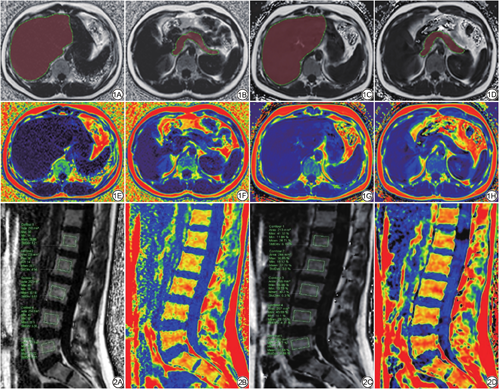

IDEAL-IQ序列经GE AW4.6工作站重建出6组图像,包括水像、脂像、同相位(in phase,IP)、反相位(out phase,OP)图像、R2*弛豫图像和脂肪分数图像。mDixon Quant序列扫描后系统自动生成上述6组图像。两名观察者(具有5年以上工作经验的放射科诊断医师)分别在两种序列的脂肪分数图像测量肝脏、胰腺及腰椎各节段椎体的FF值。肝脏与胰腺:将IDEAL-IQ序列及mDixon Quant序列的FF像导入Intelli Space Portall Version 7 (ISP)工作站,两名观察者通过3D容积提取tumor tracking软件进行半自动分割,各层面图像包含全部肝脏和胰腺,手动勾画调整边缘,得全肝脏、全胰腺FF值(图1)。腰椎:选取L1~L5椎体矢状位最大层面,两名观察者手动放置长方形ROI,面积为200~230 mm2,避开椎体头尾侧的终板、软骨和椎体前后缘骨皮质,得各椎体FF值(图2)。

IDEAL-IQ和mDixon Quant序列扫描所获得的肝脏、胰腺及腰椎椎体(L1~L5)FF值差异均无统计学意义(P>0.05;表4,图3)。